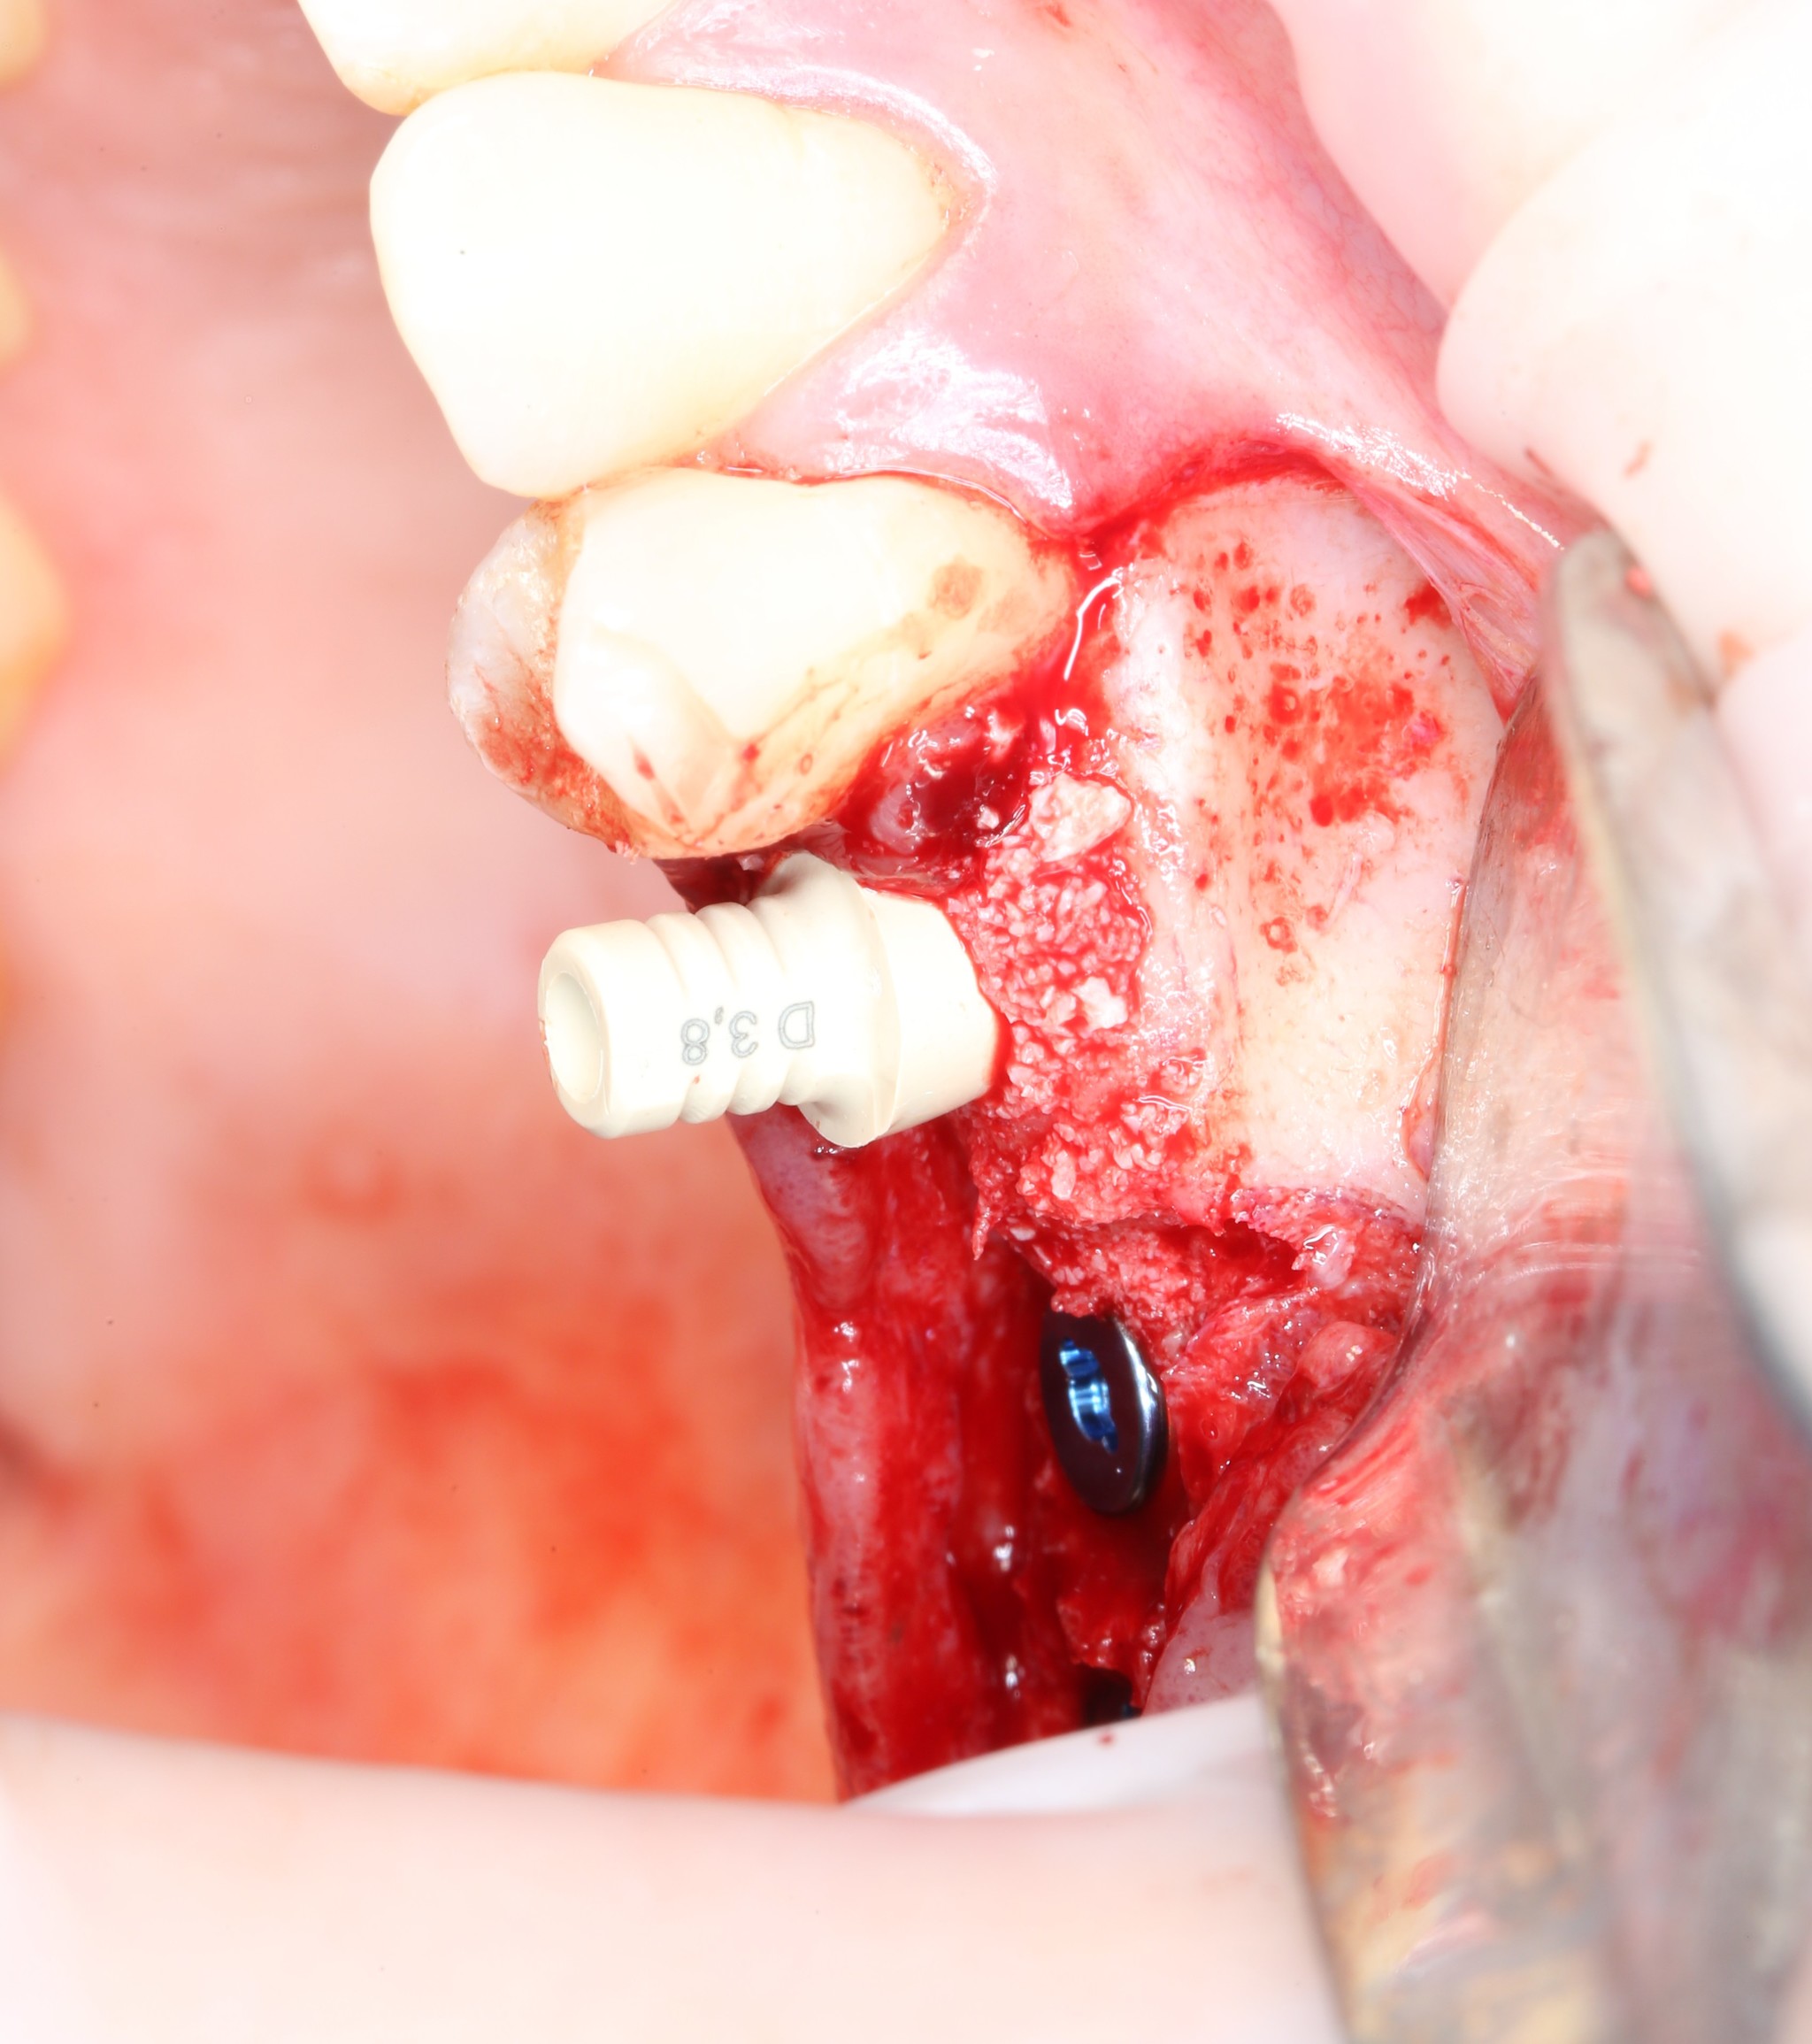

Имплантат выглядит так:

Серая часть — сам имплантат. Синяя часть — так называемый временный абатмент. В основном он выступает в роли имплантодержателя. После того, как имплантат установлен, абатмент выкручивается, как конструктор, специальной отверткой,

Фото для понимания масштаба:

а на его место вкручивается заглушка. Она устанавливается в том случае, если невозможно сразу установить формирователь десны. Тогда имплантат и все составляющие его части находятся полностью под десной, а значит, в полости рта после операции мы ничего не увидим. Ну, за исключением швов. При таком раскладе формирователь устанавливается уже после того, как имплантат приживется.

Производится установка имплантатов: